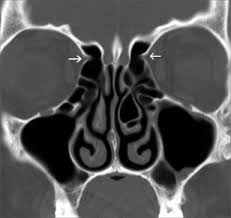

C – Cribiform plate (keros classification) – to assess the depth of olfactory fossa, length of lateral lamella, symmetry, slope or any dehiscence.